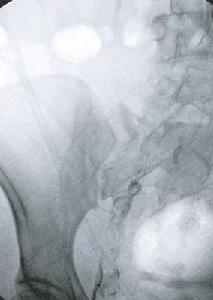

(一) 上行性靜脈造影可了解血栓的部位和範圍。病人仰臥取半直立位頭端高30~45o,先在踝部扎一橡皮管止血帶,壓迫淺靜脈用12號穿刺針直接經皮穿刺入足背,淺靜脈在一分鐘內注入40%泛影葡胺80~100ml,在電視螢幕引導下先攝小腿部X片,再攝大腿及骨盆部X片注射造影劑後,再快速注入生理鹽水以沖洗靜脈管腔,減少造影劑刺激,防止淺靜脈炎發生。